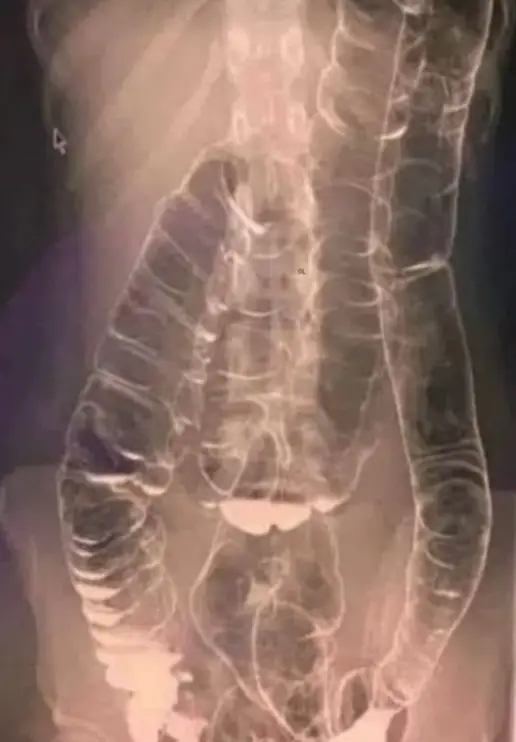

A startling X-ray photo of a woman who experienced two weeks of constipation shocked doctors.

Unable to accommodate the excessive buildup of waste, her colon enlarged significantly, reaching up towards the chest and close to the heart.

The chronic constipation led to the colon’s folds – that are vital to its functionality – to disappear.